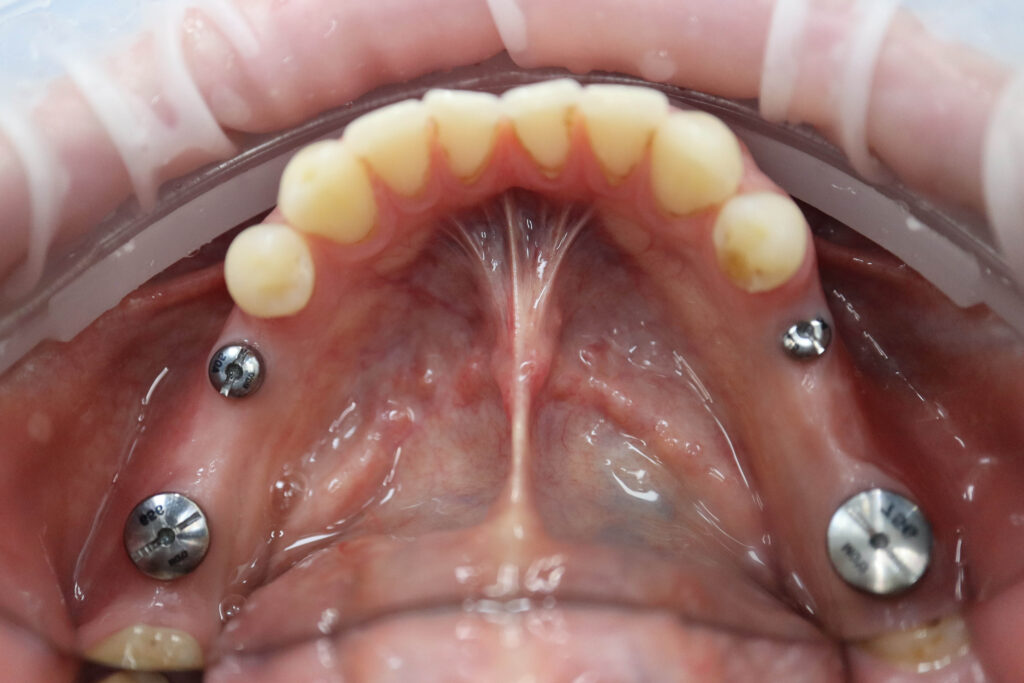

Процесс работы

Что было сделано:

На верхней и нижней челюстях были установлены 6 имплантатов Megagen Anyone.

процесс имплантации